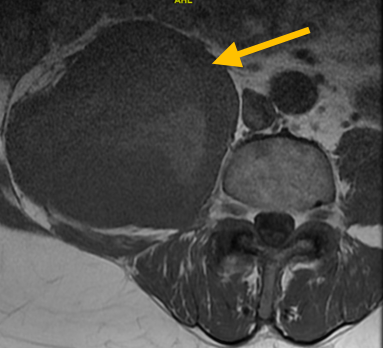

Radiographic imaging is used to help form a diagnosis of UPS. These include X-Ray, MRI, CT and Bone Scans

An example of an MRI is shown.